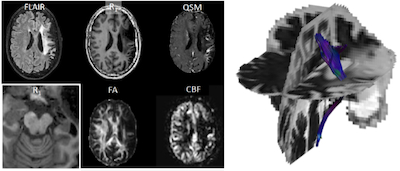

Three-year Follow-up Quantitative MRI And Recovery Assessment After Endovascular Treatment In Acute Ischemic Stroke

Methods: We executed a quantitative 3T MRI protocol (FLAIR, diffusion MRI, R1, R2*, Quantitative Susceptibility Mapping, Arterial Spin Labeling) after 37 (IQR: 28-38) months in patients from the MR CLEAN No-IV trial who received a 24-hour post-EVT MRI (DWI, FLAIR, SWI). Lateral ventricular volume difference was computed at both time-points to quantify atrophy. Long term MRI was also used to quantify iron deposition (R2*) and volume difference in subcortical nuclei relative to the contralateral nuclei. Long term recovery was defined using daily activity scores from EQ5D5 questionnaire. A Bayesian paired T-test of ventricular lateral atrophy between 24-hour and long term MRI was performed, and a Bayesian correlation of baseline clinical and 24-hour lesion characteristics with long term MRI outcomes (Bayes Factor (BF)<3: no/weak; BF>3: moderate; BF>20: strong evidence).

Results: We included 24 patients with a 24-hour and long-term MRI protocol. Median age was 64 (51-75) years, 11 (46%) patients were randomized to receive intravenous thrombolysis (IVT) prior to EVT, and 19 (79%) patients had an MCA occlusion. Functional independence (mRS 0-2) at 90 days (21 (88%) patients) and long term (20 (83%) patients) was comparable. Ventricular lateral atrophy was observed (BF=4.105), and higher baseline blood pressure and poorer collaterals were associated with larger long term lateral ventricular atrophy (BF: 11, 11, 4.3 respectively). Lower ASPECTS and poorer collaterals were associated with higher thalamic volume difference (BF=111, 11 respectively). Lastly, lower hippocampal volume and iron deposition were associated with reduced long term daily activity (BF=26, BF=4).

Conclusion: While functional independence in our cohort remains comparable over time, baseline, clinical, and treatment characteristics point to long-term brain degradation, which in turn impacts the ability of patients to perform daily activities.